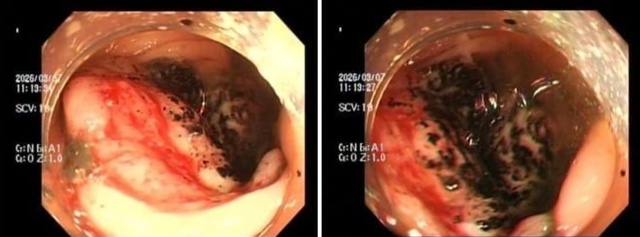

Hình ảnh nội soi đại tràng ghi nhận tổn thương dạng khối u, bề mặt loét và có dấu hiệu chảy máu

ẢNH: BVCC